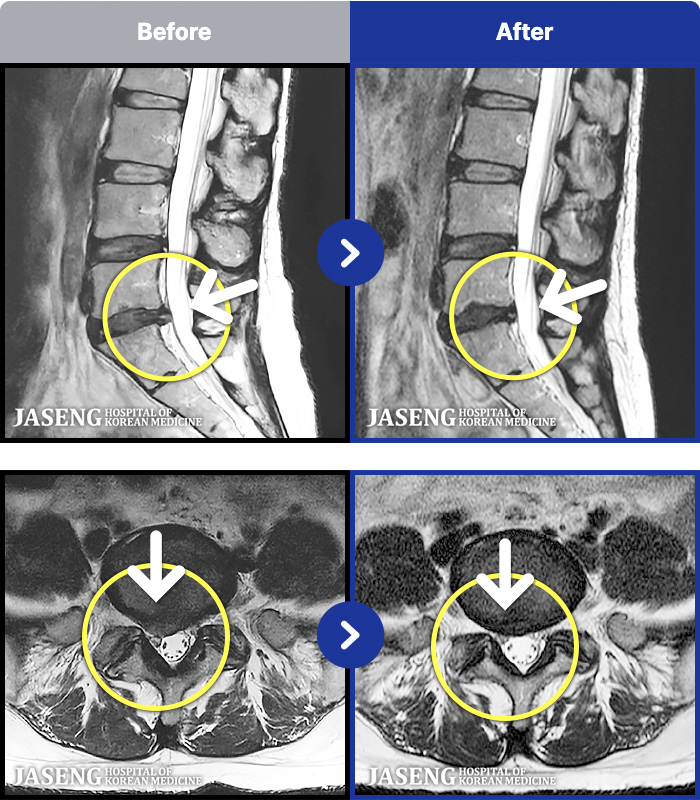

[ϻ] 24.07.25~25.08.01

ȯںп Ǹ ǿ ԿǾ, ο ġ ۿ Ƿ ġḦ Ͻñ ٶϴ.